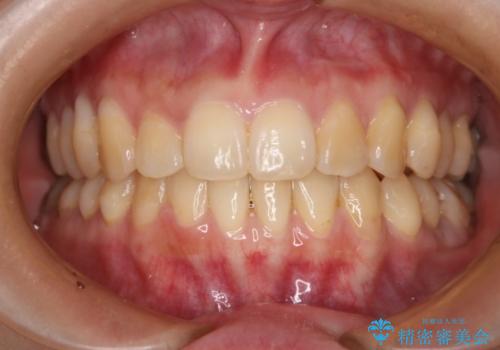

- 前歯のガタつきの改善を主訴に来院された患者様です。

ガタつきによる上顎正中の空隙や歯の突出感も気にされていました。

費用を抑えたいとの事だったので歯の移動量なども考慮し、インビザライン・ライトパッケージでの治療を計画しました。

インビザライン・ライトパッケージでは歯の移動量が限られている分、費用と期間を抑えて治療することが出来ます。